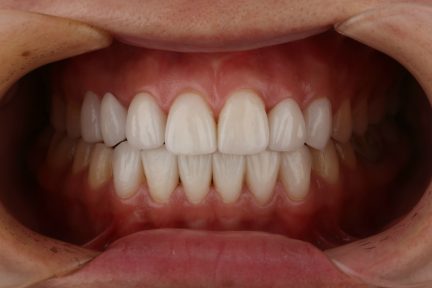

État final

Résultats obtenus

- Relation de Classe I obtenue

- Guidage fonctionnel des canines des deux côtés

- Surplomb et recouvrement normaux obtenus

- Ligne esthétique du sourire obtenue

- Cas où tous les objectifs de traitement ont été atteints

- Arcades harmonieuses obtenues

- Après traitement orthodontique, la partie supérieure droite 3, un implant posé et toutes les dents antérieures ayant reçu une restauration esthétique ont été utilisées.

- Le patient était très satisfait de l'effet curatif.

- Il est à noter que ce cas a été réalisé en une seule fois, aucune finition ne fut nécessaire.